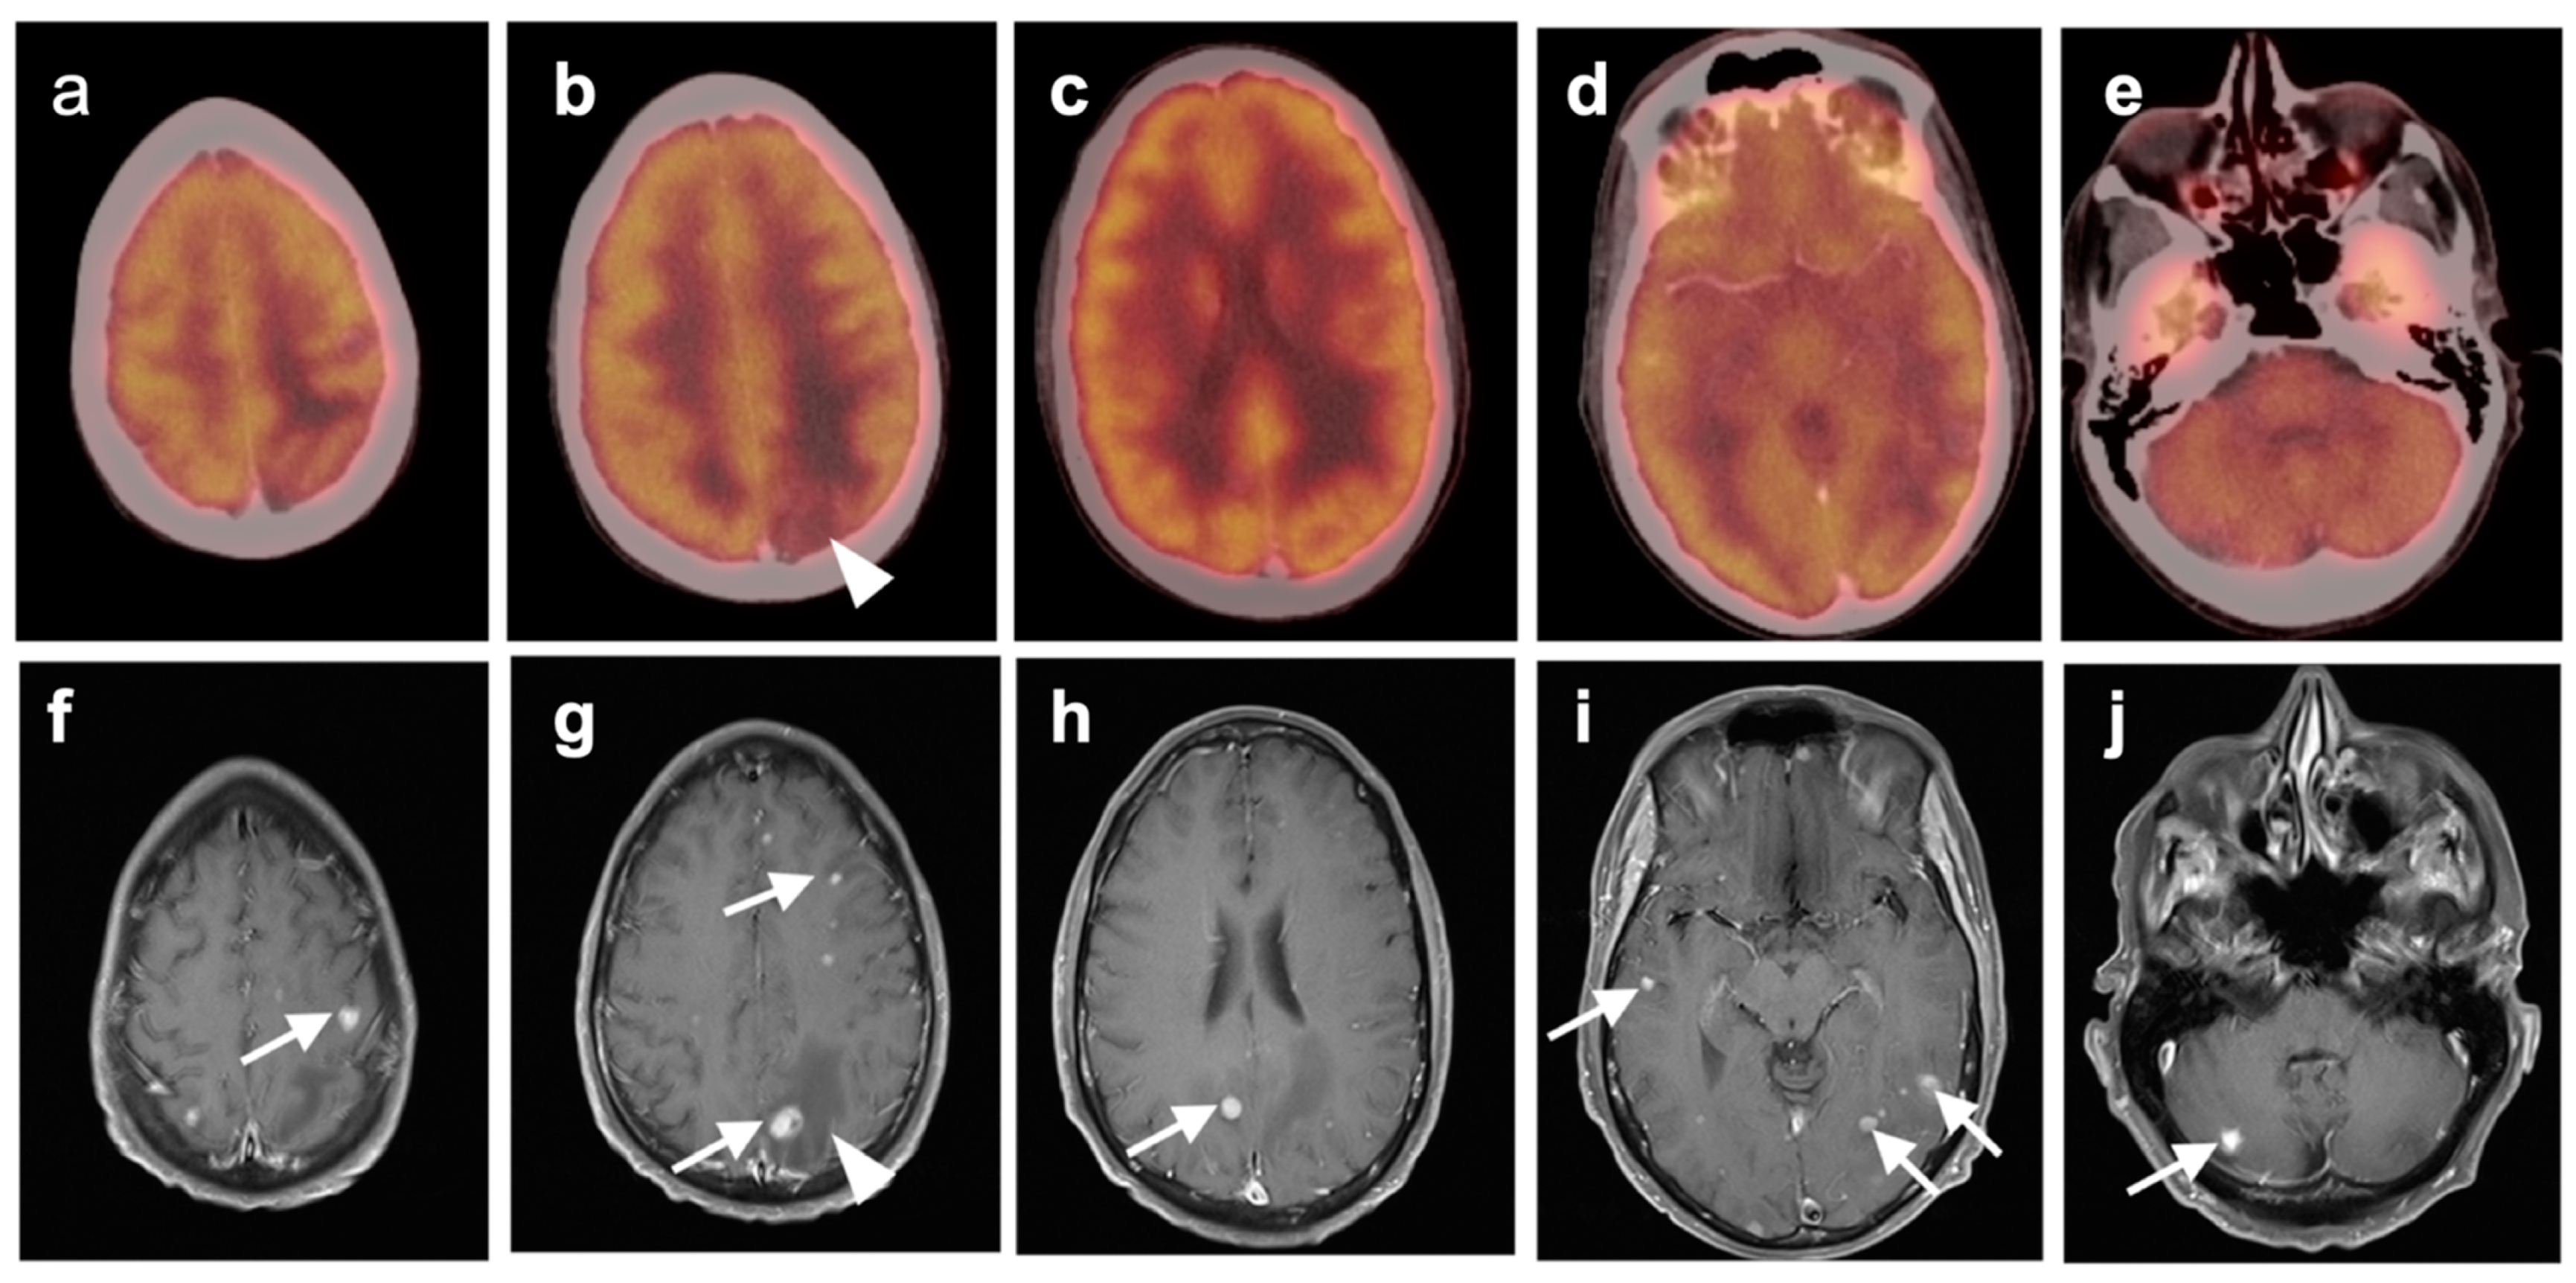

3.5. Brain Metastases

3.6. Response to Therapy